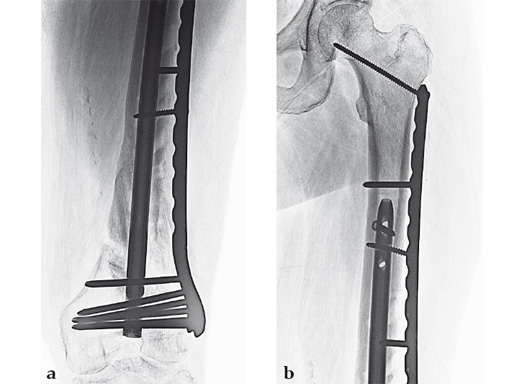

Case 1: A 30-year-old man was involved in a motor vehicle collision and sustained an isolated extraarticular multifragmentary supracondylar femoral fracture (33-A3).

Case 2: A 69-year-old man following revision total knee arthroplasty with a megaprosthesis, requiring an osteotomy of his femoral shaft for realignment of his femoral component. The patient developed a nonunion of his osteotomy and subsequently fractured the stem of his megaprosthesis.

Surgical treatment of this nonunion consisted of compression plating using the VA-LCP Curved Condylar Plate. The arthroplasty components were stable. The proximal piece of the stem was extremely well fixed. Variable-angle locked screws were targeted between his femoral shell and stem in the distal segment allowing excellent distal fixation such that an articulated tensioning device could be attached proximally and the nonunion could be compressed and the alignment improved.

Case 3: A 53-year-old man with hypotestosteronism, low vitamin D levels, and calcium metabolism problems. Recalcitrant atrophic nonunion of his distal femur after three surgical attempts with an extension and flexion contracture of his knee.

The VA-LCP Curved Condylar Plate was used to avoid previous enlarged screw holes and allow for stable fixation in the patient's osteoporotic distal segment. Secondary to his metabolic and mechanical problems, the decision was made to proceed with an endosteal implant and place interlocking screws through that implant from the VA-LCP Curved Condylar Plate. The combination of the retrograde/antegrade femoral nail and VA-LCP provides a very stable mechanical environment for the expected prolonged healing response.